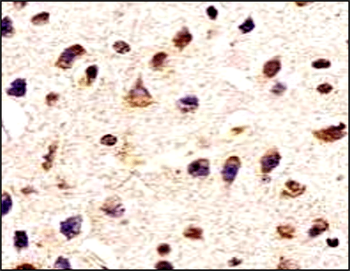

Immunohistochemical analysis of paraffin embedded Human astroglioma tissue labeling Tau with orb1294394 at 1/300.

Immunohistochemical analysis of paraffin embedded Human brain tissue labeling Tau with orb1294394 at 1/200.

Immunohistochemical analysis of paraffin embedded mouse Alzheimer’s tissue labeling Tau with orb1294394 at 1/1000 RT 1hr. Epitope Retrieval methods: Citrate Buffer, pH 6.0.